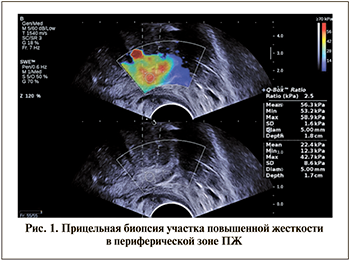

На втором этапе пациентам выполняли системную пункционную биопсию из 12 точек под контролем ТРУЗИ и трансректальную прицельную биопсию ПЖ из подозрительных участков (осуществляли забор до 4 столбиков ткани из каждого гипоэхогенного и/или жесткого очага в периферической зоне) (рис. 1). При этом во всех случаях проводили раздельную маркировку биоптатов с указанием областей забора при системной и прицельной биопсии и выбранного метода таргетирования при прицельной биопсии. Саму манипуляцию проводили под местной анестезией 1%-ным раствором лидокаина и/или гелем «Катеджель» с использованием биопсийного пистолета Bard Magnum и игл 18G.